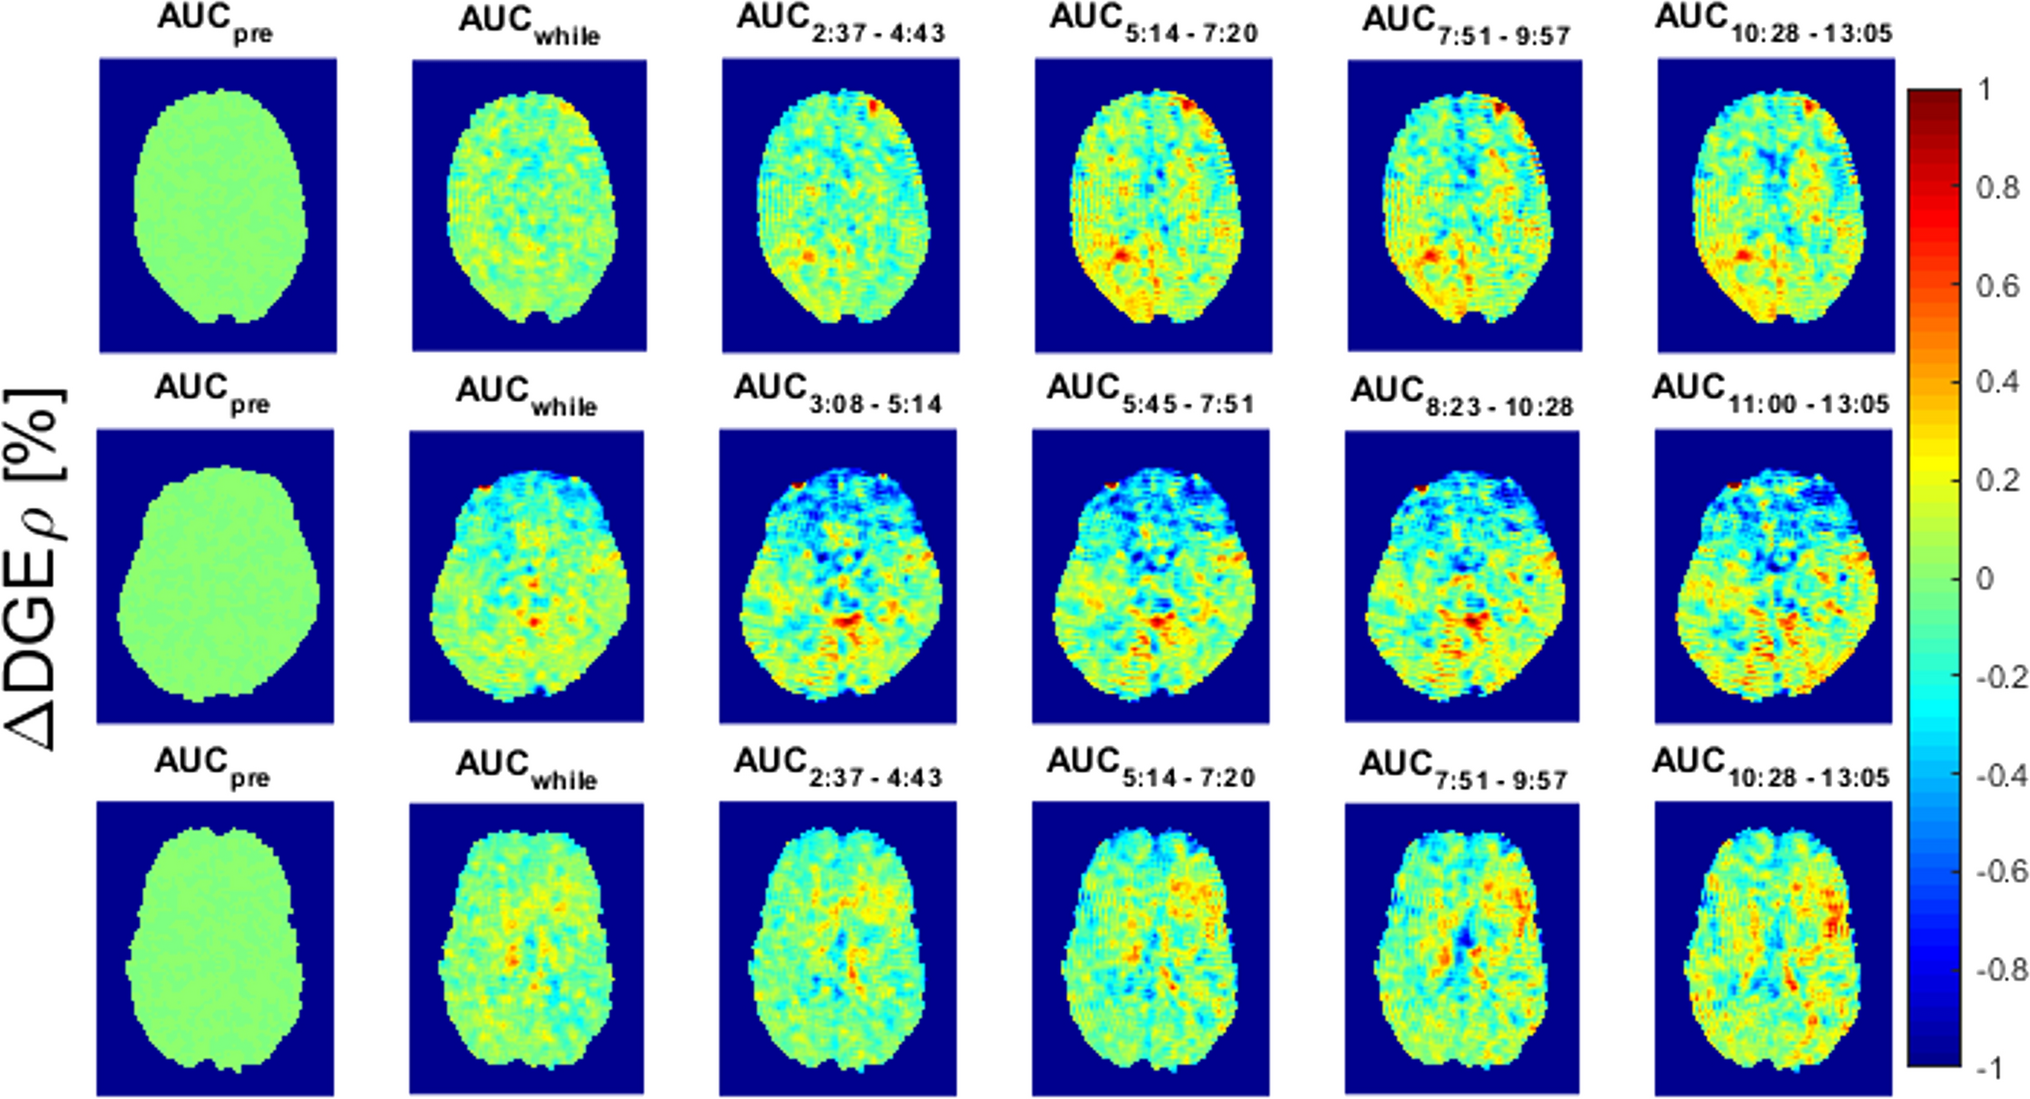

Fig. 2

∆DGE⍴ AUC maps for patients 8 (1st row, slice 6). 4 (2nd row, slice 7) and 11 (3rd row, slice 6). The maps show the AUC during different timeframes: mean ∆DGE⍴ values before injection (1st column), during injection (2nd column) and after the injection (3rd-5th column). The time in the subscript indicates the timeframe after the beginning of the injection. Supplemental Fig. 1: ΔDGEρ at 8–10 min post-injection for each measured offset: each box plot consists of all voxels within the respective ROIs. ROIs of contrast-enhancing tumor, of tumor necrosis, of T2-hyperintense tumor without contrast enhancement, and in normal-appearing white matter were analyzed. Similar effects were measured at all offsets

Range and dynamics of motion differed between patients. Patients (no. 1, 7 and 9) with sudden shifts in the position showed more obvious motion artifacts than a constant small shift over time. In patient no. 1 movement was minimal until the late scans (around 10 min after d-glucose injection) where a sudden move was identified; therefore, evaluation was possible until this point of time. Patient no. 7 and 9 were excluded from statistical evaluation due to severe motion artifacts. No increase in DGEρ signal was seen in patients with no signs of a blood–brain barrier breakdown (no. 2, 4, and 6). In none of these patients was a pseudo-CEST contrast due to movement visible. Patients with a strong enhancement and necrosis (no. 1, 3, 8, 9 and 10), and also two patients (no. 5 and 11) with a faint enhancement showed a DGEρ signal increase starting approximately 4 min after injection with a maximum increase of ∆DGEρ between 0.2 and 0.4% after approximately 9 min, whereas tumor-unaffected white matter regions did not show any significant DGEρ increase (see Figs. 1, 2).